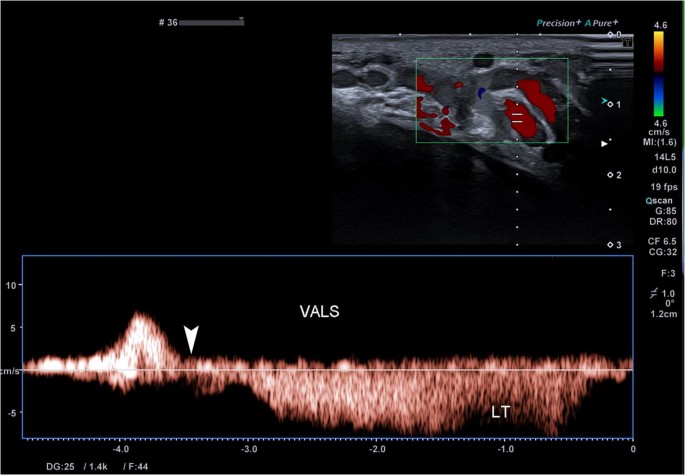

Ultrasound Evaluation Of Varicoceles Guidelines And